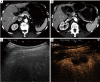

Background: To assess the technical success of contrast enhanced ultrasound (CEUS) guided biopsies of liver lesions poorly visualized on B-mode ultrasound.

Methods: Patients were selected during the procedure based on the real-time clinical scenario of unsatisfactory B-mode ultrasound lesion visualization and all patients would have otherwise undergone CT guided liver lesion biopsy. A total of 26 patients underwent CEUS guided biopsy and were included in this retrospective analysis. The review of the patients' files included demographic information, lesion characteristics on imaging, procedural details and pathology outcome. Technical success was defined as concordance between the radiological findings, pathology report and clinical follow-up-demonstrating lack of need for re-biopsy or re-biopsy with identical pathological results. Patients with less than 2 months follow-up were excluded from the study.

Results: CEUS guided liver biopsy was successful in 23 out of 26 patients (88.5%). The average procedure time was 30.7±12.3 minutes and the average lesion size was 2.2±1.7 cm. The majority of lesions (80.8%) were hypoenhancing on the delayed phase of CEUS. The mean number of samples taken from each lesion per procedure was 3.2 (±1.7).

Conclusions: CEUS guidance biopsies of focal liver lesions (FLL) that were difficult to visualize on B-mode ultrasound demonstrated high success rate and may be an evolving image guidance modality in selected patients to avoid CT guided procedures.